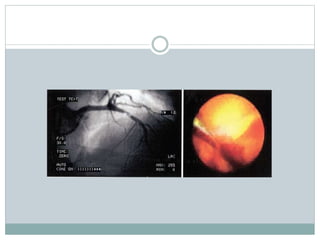

Angiogram

 Coronary angiogram delineate the coronary lumen but

does not provide any information about the vessel

wall.

 The finding of multiple complex lesions in an

angiogram- sign of an active systemic inflammatory

process, may produce numerous vulnerable plaques in

the future.

 Complex lesions have some peculiar angiographic

features: intra-luminal filling defects (consisting with

thrombus), presence of contrast and hazy contour

beyond the vessel lumen (consisting with plaque

ulceration), irregular margins and overhanging edges

(consisting with plaque irregularity and, possibly,

Angioscopy

Based on fiber-optic transmission of visible light .

-Advantage:

-anatomic

-simple

-Disadvantage:

-subjective

-just surface of plaque is visualized

-limited spatialresolution

-needs a proximal occluding balloon

48

 Permits direct visualization of plaque surface.

 Plaque colour is graded as:

 White-thickcaps(400 mic)

 Lightyellow

 Yellow :thinnercaps(80 mics)

 Glistening yellow: thinnestcaps(10-20mics)

 Glistening yellow plaques are strong predictors of TCFAs and ACS (68% -

Uchida et al)

 Requires removal of blood